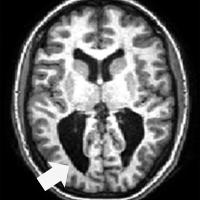

Cross-section of fMRI brain scan with arrow pointing to dark area

The National Institutes of Health sponsored its first-ever workshop on cerebral visual impairment (CVI), an umbrella term for subnormal vision resulting from brain injury during development.

Cerebral (cortical) visual impairment (CVI) is a condition that interferes with the ability of the brain to process information from the eyes, and it has become a leading cause of visual impairment in the U.S.